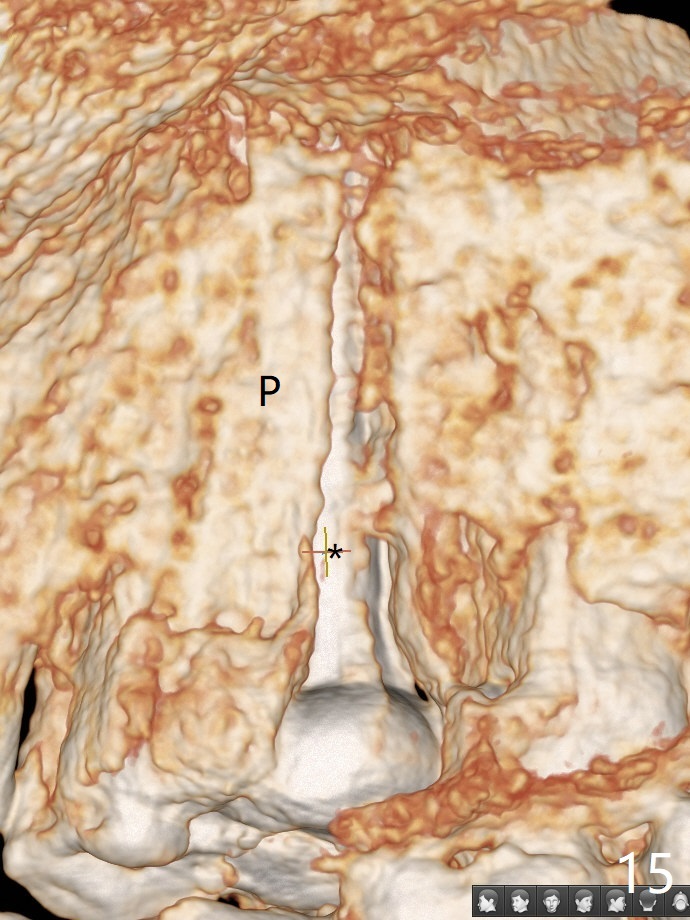

In fact there is a small buccal fistula, which is communicated with the underlying implant threads. Although preop CT shows that the buccal crest is lower than the palatal (3.8x13 mm, Fig.10 P) one, intraop finding of missing buccal plate should dictate a shorter implant (Fig.11) or onlay graft to avoid periimplantitis. Regeneration of the bone plate is limited. Later the fistula disappears with formation of a concavity (Fig.13). There is no symptom. Is bone graft necessary with a remote incision? 3-D images of CT taken 1 year 5 months post cementation show possible mesiobuccal and distopalatal bony defects (Fig.13-16). It is possible that bone graft was placed enough palatal (Fig.16). DO composite at #3 is redo satisfactorily (Fig.17 *).